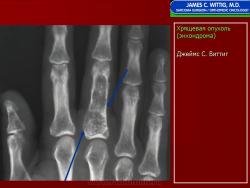

Энхондрома (син.: хондрома, центральная хондрома) — доброкачественная хрящевая опухоль, расположенная в костномозговом канале (интрамедуллярно). Встречается в 10 % случаев от общего числа доброкачественных опухолей костей. Считается, что она возникает из эктопически расположенных островков хряща, отщепившегося от пластинки роста на ранних этапах онтогенеза. В ряде случаев опухоль остается бессимптомной и обнаруживается случайно при рентгенологическом исследовании. В других случаях возникают боль и припухлость. Обычно болезненными становятся все энхондромы фаланг. Наиболее частая локализация: фаланги, главным образом, пальцев кистей, проксимальный конец плечевой кости, проксимальный или дистальный концы бедренной кости. При рентгенологическом исследовании в энхондроме определяются просветления с участками минерализации. Тень кости становится более широкой, кортикальный слой сохраняет целостность, но истончается. В редких случаях энхондрома имеет вид эксцентрически растущего экзофитного новообразования. Макроскопически опухоль представляет собой голубовато-белую полупрозрачную хрящевую ткань, в которую вкраплены желтоватые участки обызвествления. Опухоль состоит из отдельных хрящевых узелков, диаметр которых варьирует в пределах 1 см.

Рентгенологическая картина хондромы представляет четко очерченный опухолевый узел. Очаги минерализации в хондромах выглядят достаточно характерно и представлены очаговыми, глыбчатыми или кольцевидными , арочными отложениями извести. Полного разрушения кортикального слоя трубчатой кости с выходом опухолевых масс в мягкие ткани не наблюдается.